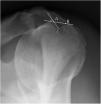

Material and MethodsA prospective study was conducted, and sixty consecutive patients proposed to shoulder arthroscopic surgery were selected. Before surgery, a radiographic evaluation was performed with a supine and a Fisk radiograph. Most supine radiographs (>75%) were non-interpretable and were excluded from the study. As some Fisk radiographs (26.7%) were also non-interpretable, that left 44 interpretable radiographs in the study. These were measured for medial opening angle, total opening angle, width and depth of the bicipital groove. The radiographic measurements and the presence of LHBT pathology, as assessed at arthroscopy, were correlated.

ResultsRadiographic evaluation of the bicipital groove showed a mean medial opening angle of 53±15o (23 – 90), a mean total opening angle of 80±26o (30 – 135), a mean width of 10.3±2.5mm (6 – 19) and a mean depth of 4.1±1.5mm (1 – 8). Men had higher medial opening angle (60 vs 50o, p=0.044) and wider grooves (11.9 vs 9.7mm, p=0.019). Twenty-five patients (56.8%) were found to have an abnormal LHBT. No correlation was found between the radiographic measurements and LHBT pathology. Only age was correlated with a LHBT lesion (61.8 vs 46.3 years, p <0.001).